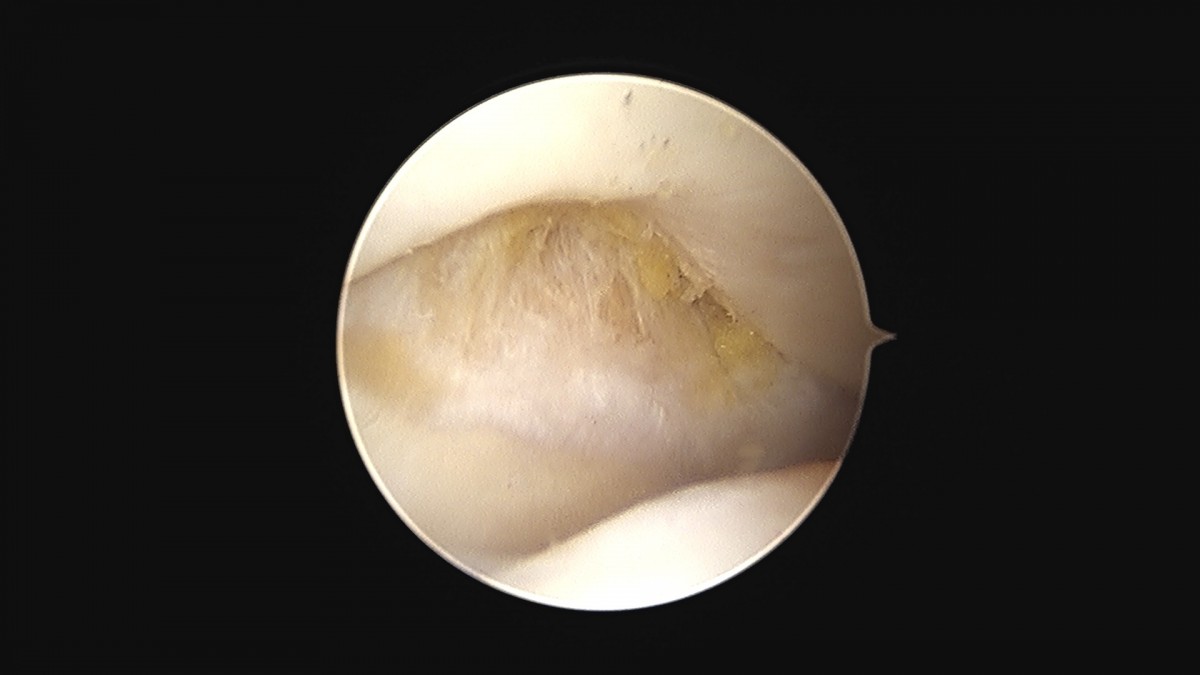

이재상원장님 무릎 변연절제술 권오O 환자

작성자 최고관리자 댓글 0건 조회 373회 작성일 25-09-16 16:11